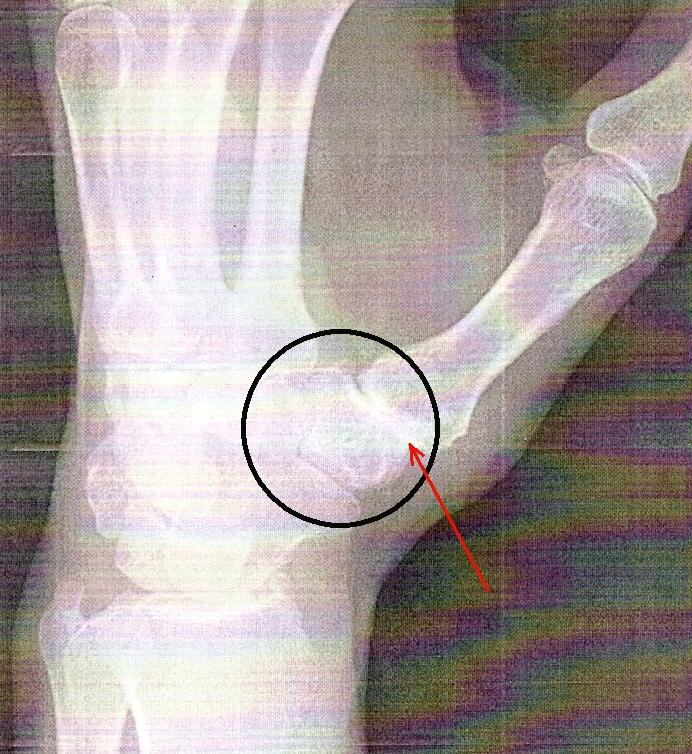

Here's a post-surgery x-ray. The trapezium was removed and replaced with a flexible plastic (maybe nylon or some other appropriate material) appliance. It has a cone shape on the end that was inserted into the end of the first bone of the thumb. |

The first cast was removed about 2 weeks after the surgery. You can see the z-shaped incision where the main work was done. The doctor also made a 2-inch incision on the bottom of my arm to harvest a piece of tendon that was used to secure the appliance. |